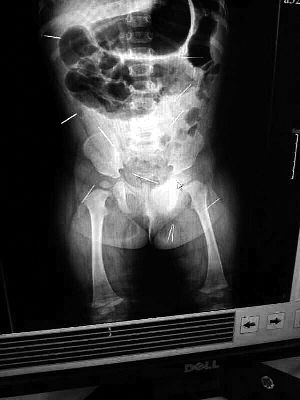

山東聊城11個(gè)月女嬰萱萱(化名)疑似被人以12根鋼針插滿臀部、腹腔等部位,昨天在兒童醫(yī)院會(huì)診后,醫(yī)生稱3根針靠近胸腔最危險(xiǎn),首批先行取出,預(yù)計(jì)將在下周二手術(shù)。孩子父母稱孩子一直由家人照顧,自家與他人并無(wú)冤怨。山東警方表示正在偵破中,不便透露案情。

“要不是當(dāng)初那幾個(gè)紅點(diǎn),可能到現(xiàn)在我們還不知道孩子身體里有鋼針!”昨天,在兒童醫(yī)院住院處,萱萱爸爸范先生稱,日前原本很愛笑的萱萱突然變得有些焦躁,一抱起來(lái)就哭,孩子母親偶然間在萱萱屁股上發(fā)現(xiàn)了幾個(gè)小紅點(diǎn)兒,原以為是蚊蟲叮咬,就醫(yī)結(jié)果卻讓人不寒而栗?!搬t(yī)院拍出的片子上,萱萱的體內(nèi)有12根鋼針,插滿臀部、腹腔、骨盆等各個(gè)部位?!狈断壬榻B,因?yàn)殇撫樢焉钊塍w內(nèi),要是孩子不哭鬧,他們很難發(fā)現(xiàn)。

北京晨報(bào)記者了解到,目前體內(nèi)的12根鋼針多分布在孩子的臀部,一根在腹部,其余3根在胸腔附近,其中一根很接近心臟。“因?yàn)楹⒆犹?,醫(yī)生們害怕取針的時(shí)候?qū)λ斐蓚?,在胸腔附近?針可能會(huì)威脅她的生命”。

截至昨晚6時(shí)許,北京晨報(bào)記者從兒童醫(yī)院宣傳部門了解到,孩子目前已經(jīng)接受完專家會(huì)診,暫定今天和下周一進(jìn)行術(shù)前檢查,如果一切順利將在下周二手術(shù),“孩子暫時(shí)沒(méi)有生命危險(xiǎn)”。